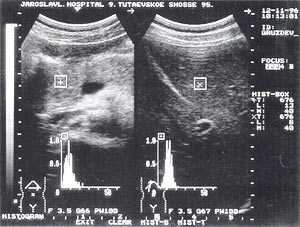

- изменение эхогенности железы: повышение - 85,6% случаев (рис. 2); нормальная - 8,6% случаев; понижение - 5,8% случаев.

Рис. 2. Острый панкреатит, повышение эхогенности поджелудочной железы (по сравнению с эхогенностью печени).